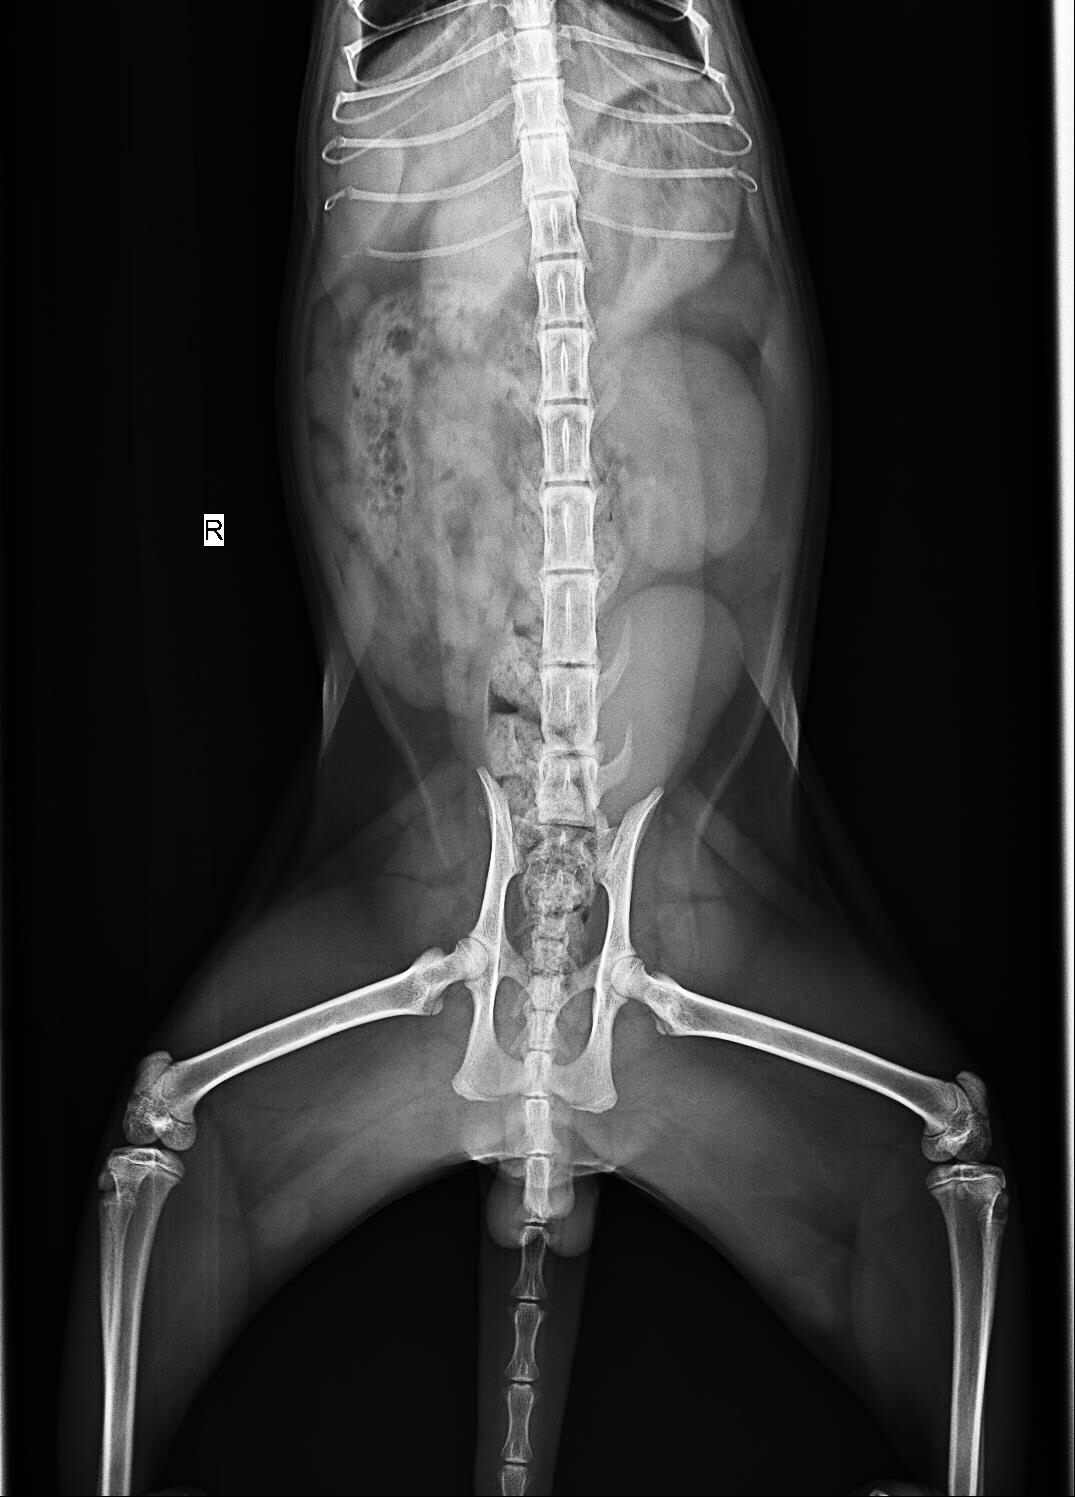

可以去折耳猫吧问问。不过尾巴那么粗还外八,还是拍个片子看看吧

尾巴看起来有点硬,检查一下比较放心

拍出来说是左肾肿大右肾萎缩…肾功能正常,拍片b超、肾功能检查总共花了近900…得到建议是半年后复查、也说折耳病并不明显、我特喵不会被杀猪了吧

但是医生说拍片来看折耳病症状不明显…我都不知道是不是遇到庸医了…

我收回标题耳朵是立的这句话…现在来看确实是一只折耳